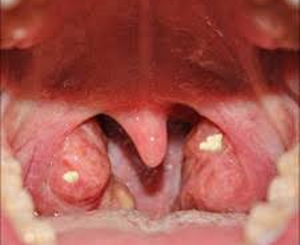

Bài thuốc chữa viêm amidan cấp

Tapchisuckhoedoisong.com 0

Trong thời tiết nóng, nhiều người có thói quen ăn uống đồ lạnh như kem, sữa chua, sinh tố lấy từ tủ lạnh; tắm nước […]